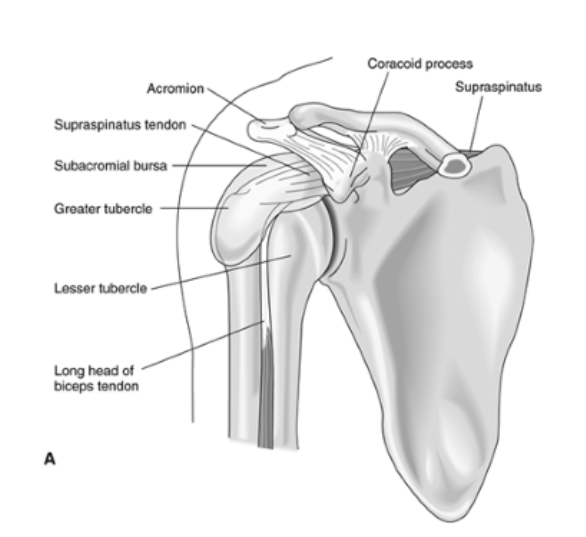

- Động (dynamic): các cơ, đặc biệt là cơ chụp xoay (rotator cuff). Các thành phần của chụp xoay bao gồm cơ dưới vai, cơ trên gai, cơ dưới gai, cơ tròn bé giúp giữ vững khớp ổ chảo-cánh tay

- Đầu dài gân nhị đầu ngăn chỏm xương cánh tay di lệch lên trên và ra trước

- Cơ trên gai giữ cho xương cánh tay khỏi đi xuống

Khoảng dưới mỏm cùng vai:

- có bao hoạt dịch dưới mỏm cùng vai